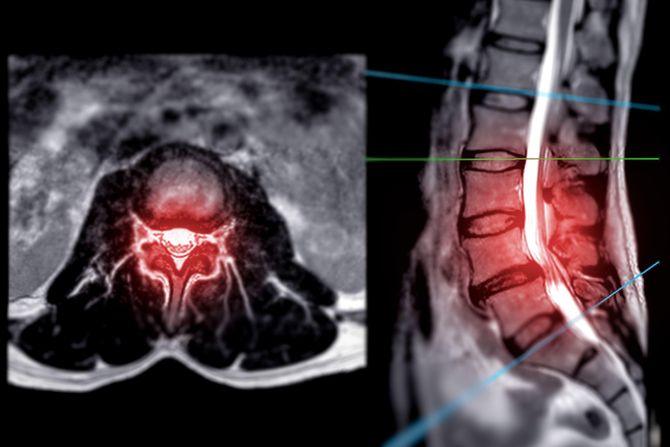

Studija je pronašla dve bitne grupe neurona kičmene moždine, jednu neophodnu za novo adaptivno učenje i drugu za sećanje adaptacija pošto su naučene. Ovo otkriće bi moglo biti od pomoći u pronalaženju načina za motorni oporavak nakon povrede kičmene moždine.

Eksperimenti na miševima putem električnih šokova kad su im noge spuštene ispod određenog nivoa pokazali su posle 10 minuta da kičmena moždina može povezati neko neprijatno osećanje sa položajem nogu i prilagoditi svoje motorne signale tako da noge izbegnu to osećanje – tako što će ostati visoko, a sve bez ikakve potrebe za mozgom. Posle 24 sata, eksperiment je ponovljen, a kičmena moždina je zadržala pamćenje prošlog iskustva.

Pošto su ustanovili i neposredno učenje i pamćenje u kičmenoj moždini, istraživači su se fokusirali na nervnu šemu koja to omogućava. Otkrili su da se noge miševa nisu prilagodile na izbegavanje električnih šokova nakon što su neuroni pri vrhu kičmene moždine bili onesposobljeni, naročito oni koji izražavaju gen Ptf1a.

S druge strane, kad su dan nakon učenja izbegavanja bili onesposobljeni neuroni u donjem delu kičmene moždine koji izražavaju gen En1 – kičmena moždina se ponašala kao da ništa nije naučeno. Takođe, pobuđivanje En1 neurona tokom prisećanja povećalo je brzinu postizanja povoljne pozicije nogu za 80%.